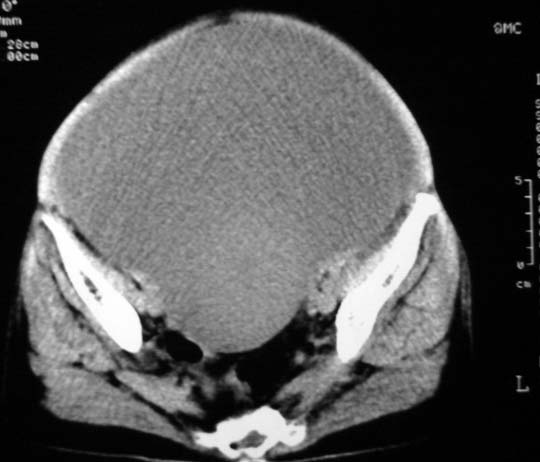

女,75岁,腹部胀大半年余,无其他症状。

考虑来源与卵巢的巨大囊腺瘤或囊肿。

真是腹大如牛,考虑卵巢巨大囊腺瘤或囊肿。

考虑来源卵巢巨大黏液性囊腺瘤。